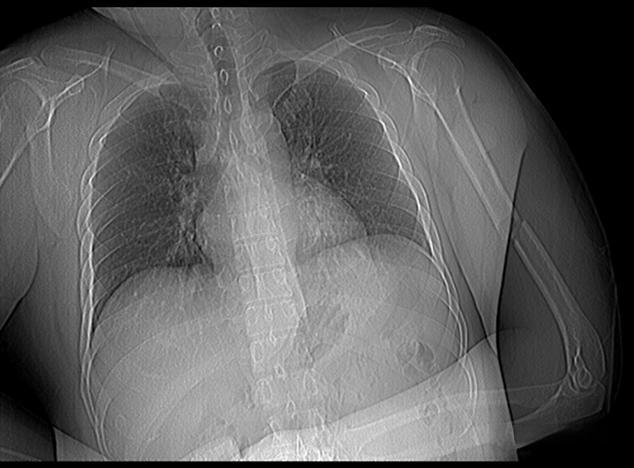

影像技师的专业判断往往直接影响着患者的治疗结果。以一例肺癌诊断为例,一位经验丰富的影像技师在阅片时发现肺部一个微小的结节,虽然计算机辅助诊断系统并未标注异常,但技师凭借多年的经验判断可能存在恶性可能。经过进一步检查,最终确诊为早期肺癌。正是这位技师的敏锐观察,为患者赢得了宝贵的治疗时间。